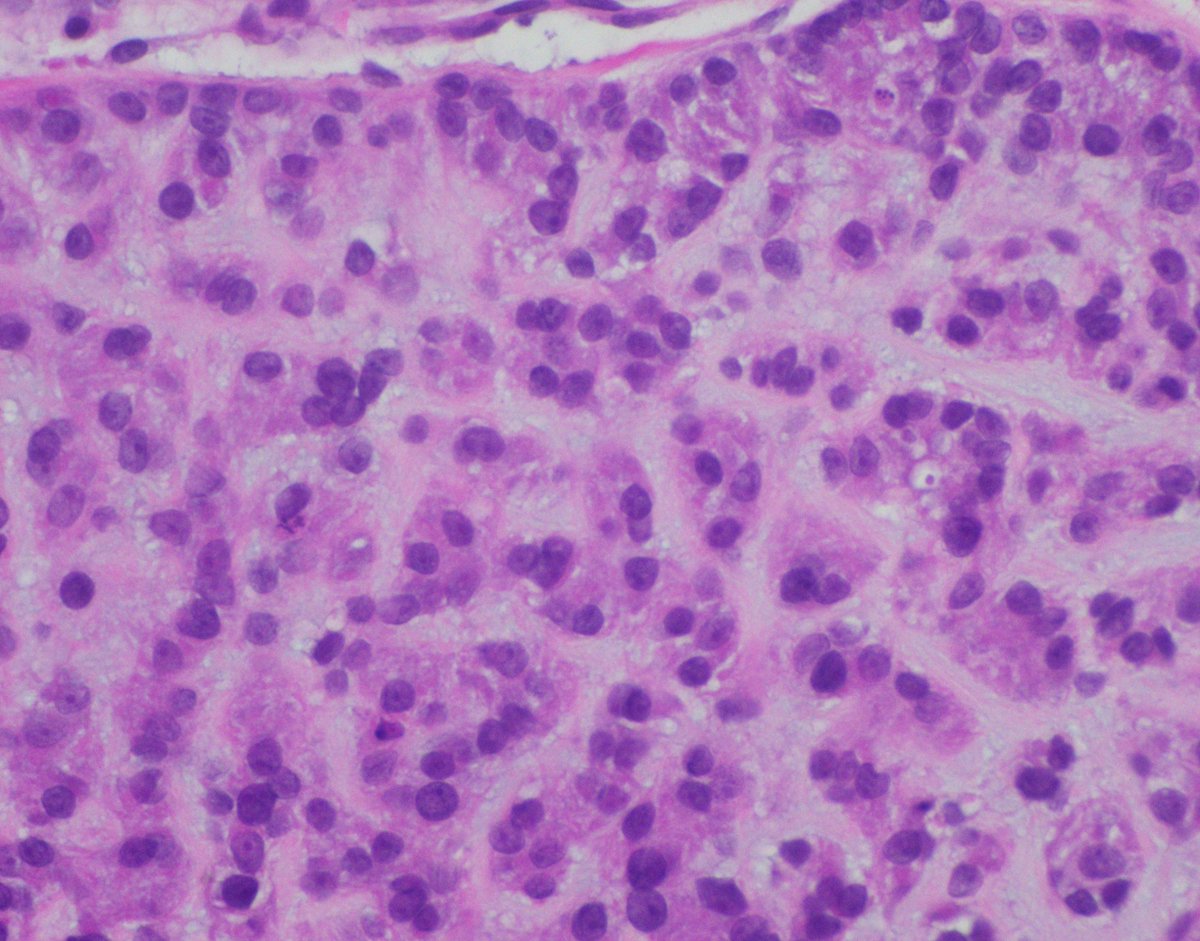

Our GI Pathology Fellowship has an unexpected opening for July 2026. Dr. Ortiz (right) and I are the program directors. We have superb cases and excellent colleagues (Drs. M. Garcia, R. Yantiss, S. Al Diffalha, O. McDonald). Send your CV to adriana.zanaty@miami.edu